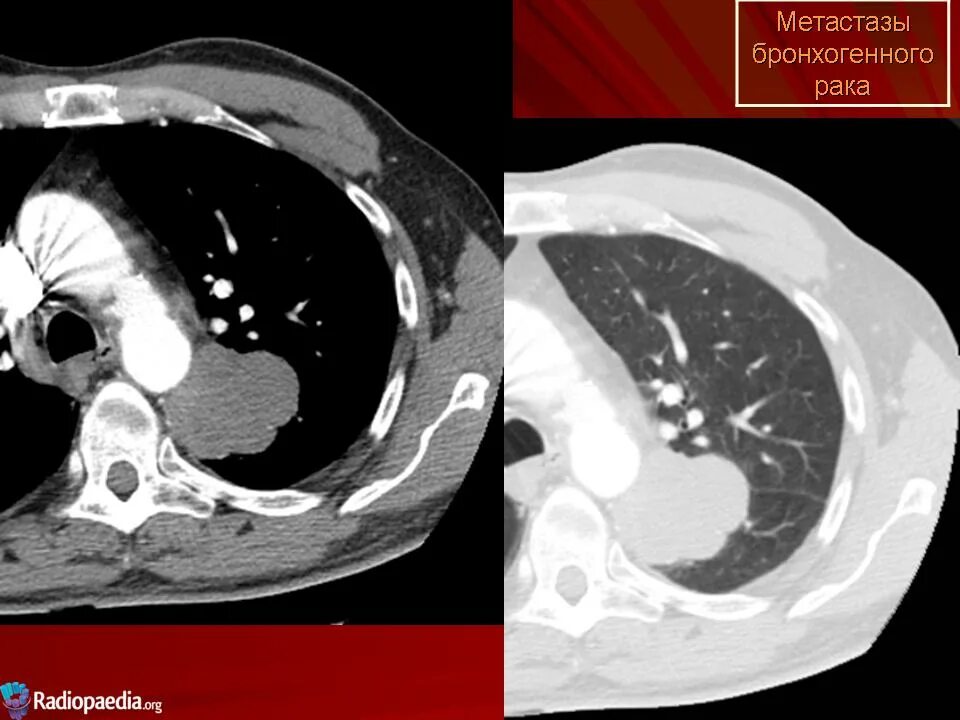

Метастазы головного мозга кт